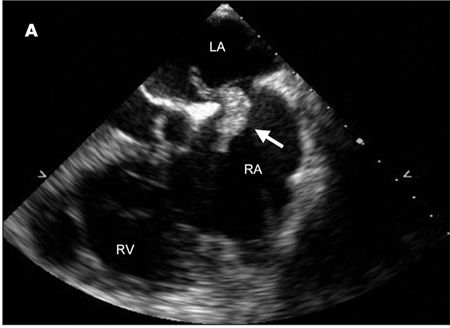

A CT scan of the chest revealed large bilateral pulmonary emboli. A heparin weight-based protocol was started, and transthoracic echocardiography was performed to look for signs of right heart strain. The imaging revealed what appeared to be 2 large echodense structures within the left and right atria. A follow-up transesophageal echocardiography (TEE) revealed a large mobile echogenic structure of 3.6 X 1.5 cm traversing the intra-atrial septum at the level of the foramen ovale, consistent with a thrombus-in-transit (A). During the procedure, the patient began retching and repeated viewing of the intra-atrial septum revealed that the thrombus had completely disappeared. An agitated saline study showed contrast bubbles passing from the right atrium (RA) to the left atrium (LA), confirming the presence of a patent foramen ovale (B).

Intracardiac thrombi are most often associated with pulmonary emboli and can be visualized on transthoracic or transesophageal echocardiography in as many as 4% to 18% of cases.1 If a patent foramen ovale is present, a thrombus can cross from the right atrial circulation directly into the left atrium. When the thrombus is not attached to any other intracardiac structure, the phenomenon is known as a thrombus-in-transit.2